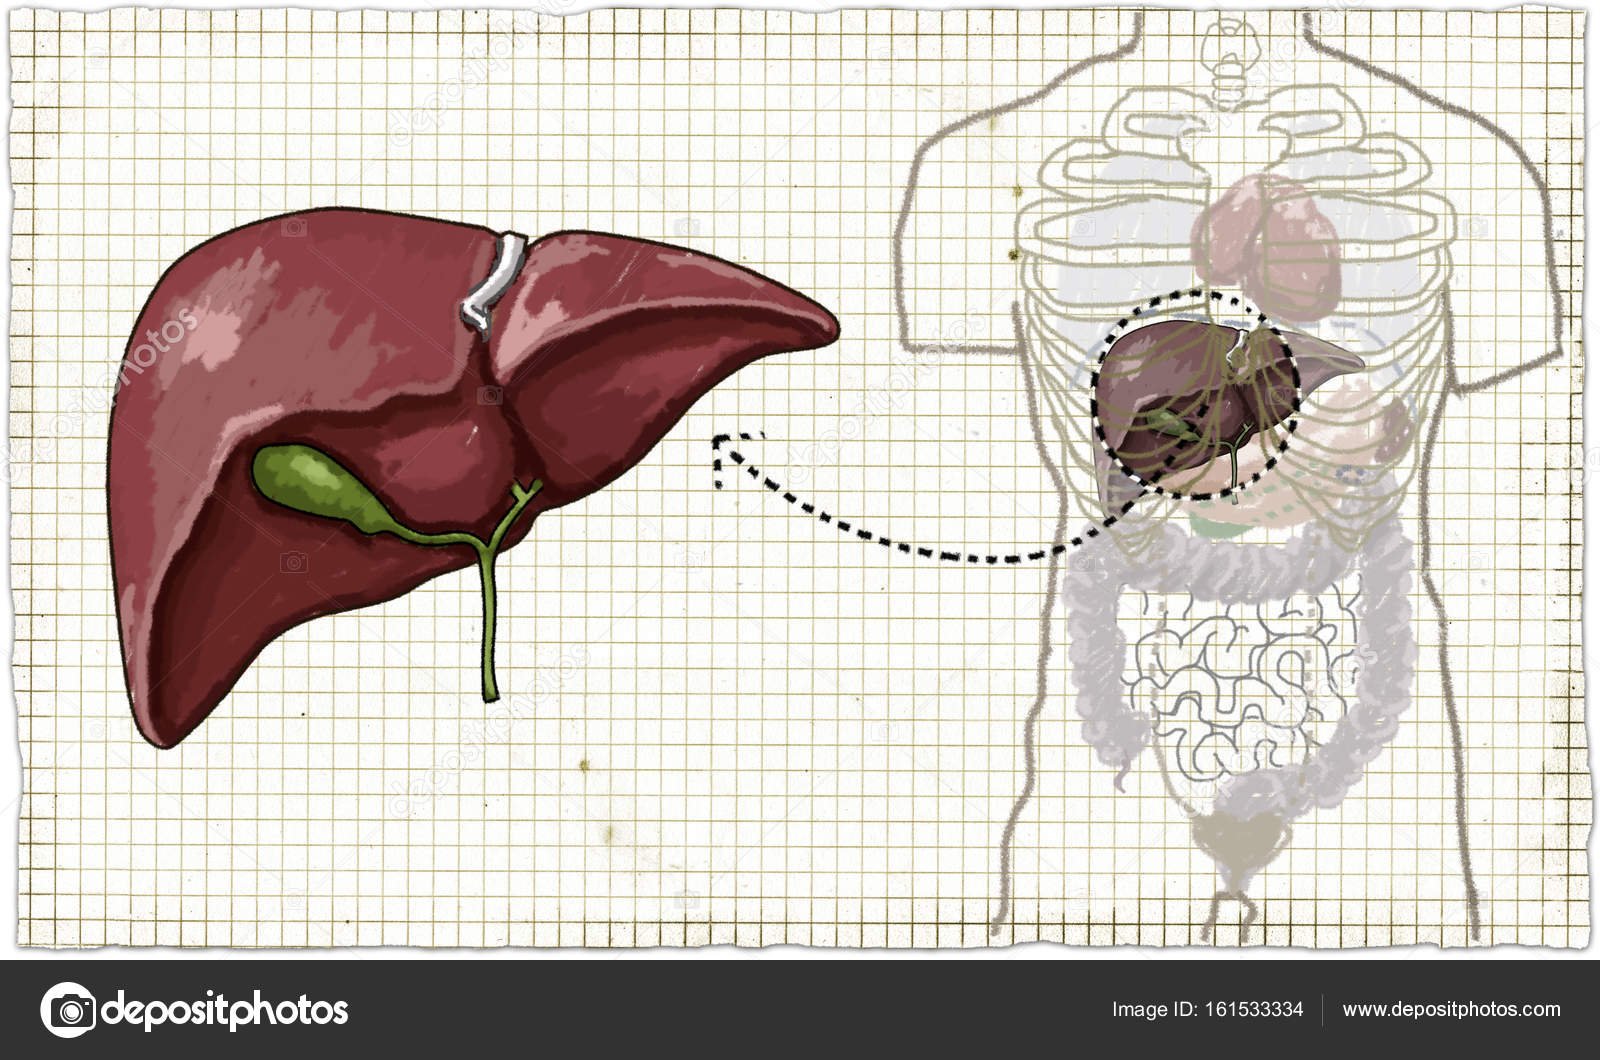

Печень, один из самых крупных и важных органов человеческого тела, выполняет множество жизненно необходимых функций, включая фильтрацию токсинов и производство жизненно важных белков. В данной статье мы рассмотрим, как наглядные изображения печени могут помочь лучше понять её структуру, функции и возможные заболевания. Использование рисунков и диаграмм делает сложные биологические процессы более доступными для понимания, особенно важно это для студентов, врачей и пациентов, стремящихся глубже изучить этот ключевой орган.

Печень рисунок